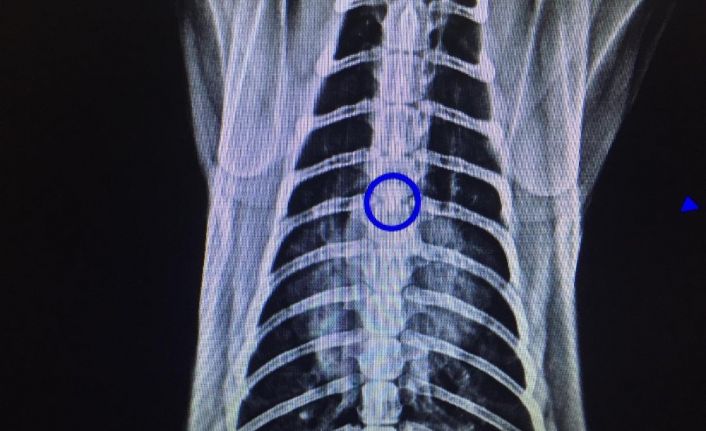

Zonguldak’ta ameliyata alınan kedinin soluk borusundan 1,5 santimlik taş çıkarıldı.

Kastamonu’da hayvanseverlerin baktığı 2 yaşındaki kedi nefes alıp vermekte sorun yaşadı. Ardından hayvanseverler hasta kediyi Kastamonu’da veteriner kliniğine getirdi. Ancak veteriner kliniğinde yeterli ekipman olmadığı için kedi Zonguldak’a nakledildi. Zonguldak Veteriner Kliniğinde röntgeni çekilen kedinin soluk borusunda 1,5 santimlik taş olduğu tespit edildi. Veteriner hekimler Önder Alkan ve Suat Ulucak tarafından 4 saat süren ameliyatla kedinin soluk borusundaki taş çıkarıldı. Yoğun bakıma alınan kedinin durumunun iyi olduğu öğrenildi.

Veteriner Hekim Önder Alkan, ’’Dün akşam Kastamonu ilinden geldi bize hastamız. Yaptığımız tetkiklerde soluk borusunda yabancı cisim tespit ettik akciğerin giriş bölgesindeydi kalbin üzerinde kötü bir solunumu vardı boğulmak üzereydi. Açık bir ameliyat geçirdi. Soluk borusundan bir taş çıktı. Zorlu bir ameliyattı 6 saat sürdü. Ameliyattan sonra solunumu düzeldi. Akciğerler düzeldi 3 günlük sıkıntılı bir durumu var. Oynarken muhtemelen oldu aşağıya kadar indi. Bir anda solunum güçlüğünden dolayı anlamış vatandaş ve hemen veterinere getiriyor ve yapılan tetkiklerde yabancı cisim görülüyor. Bu ameliyat için otomatik solumun sistemi gerekiyor. Bu sistem olan yerlerde bu ameliyatlar yapılıyor. Zor ve riskli bir ameliyat” şeklinde konuştu.